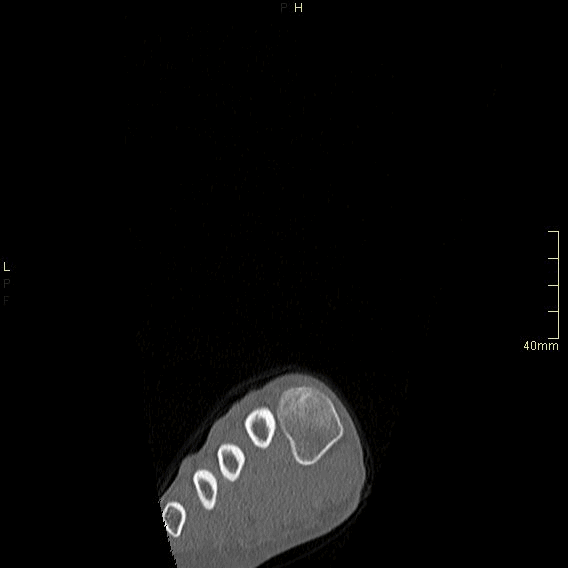

CT Ankle Contrast- Soft tissue window (coronal)

CT Ankle Contrast- Bone window (coronal)